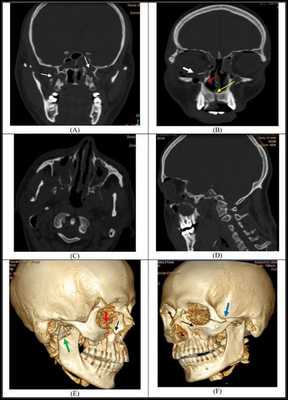

Симптоматика переломов костей средней зоны лица многообразна, поэтому для постановки точного диагноза требуется выполнение рентгенологической диагностики. Самым современным и точным методом является компьютерная томография . С её помощью челюстно-лицевой хирург имеет возможность точно определить локализацию линии разъединения костных фрагментов и тип перелома, выбрать наиболее адекватную и малотравматичную тактику лечения [11] .

При подозрении на перелом верхней челюсти обязательна консультация невролога, так как в абсолютном большинстве случаев нарушение целостности костей лицевого скелета сопровождается сотрясением головного мозга. При констатации перелома основания черепа пациента обязательно должен осмотреть нейрохирург, офтальмолог, терапевт и иногда лор-специалист. При сочетанных травмах (например при ДТП) привлекаются общие хирурги, травматологи.

Самым современным и адекватным методом лечения на данный момент является остеосинтез (фиксация титановыми накостными конструкциями) переломов верхней челюсти. Это хирургическое вмешательство, выполняемое из внутриротовых разрезов. При таком варианте лечения можно точно сопоставить и зафиксировать фрагменты для создания условий их сращения [7] .

При лечении высоких переломов также используется коронарный доступ, который позволяет создать косметичный и широкий доступ к костям всей средней зоны лица и глазницам [5] . Своевременное выполнение остеосинтеза позволяет предотвратить поздние послеоперационные осложнения, облегчить реабилитацию пациента и ускорить сроки выздоровления.